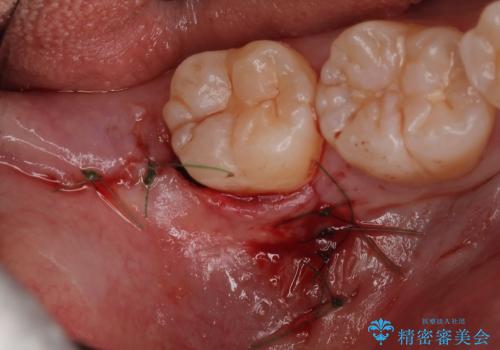

親知らず抜歯

- 20代女性

- 1ヶ月

- 2-5回

- 親知らずを抜きたいとのことで来院。CTで神経の位置などを確認し、抜歯を行いました。1週間後には抜糸に来院予定です。

しっかり麻酔が効いていることを確認し抜歯を行いました。

親知らずがあると清掃性が悪くなるため手前の歯の虫歯のリスクが上がるので抜歯をおすすめします。